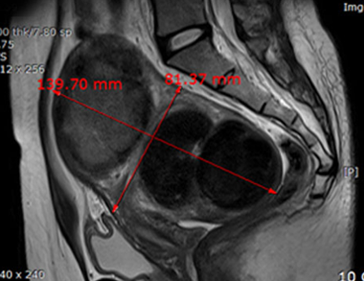

자궁근종 치료 사례

• 시술 전

시술 후